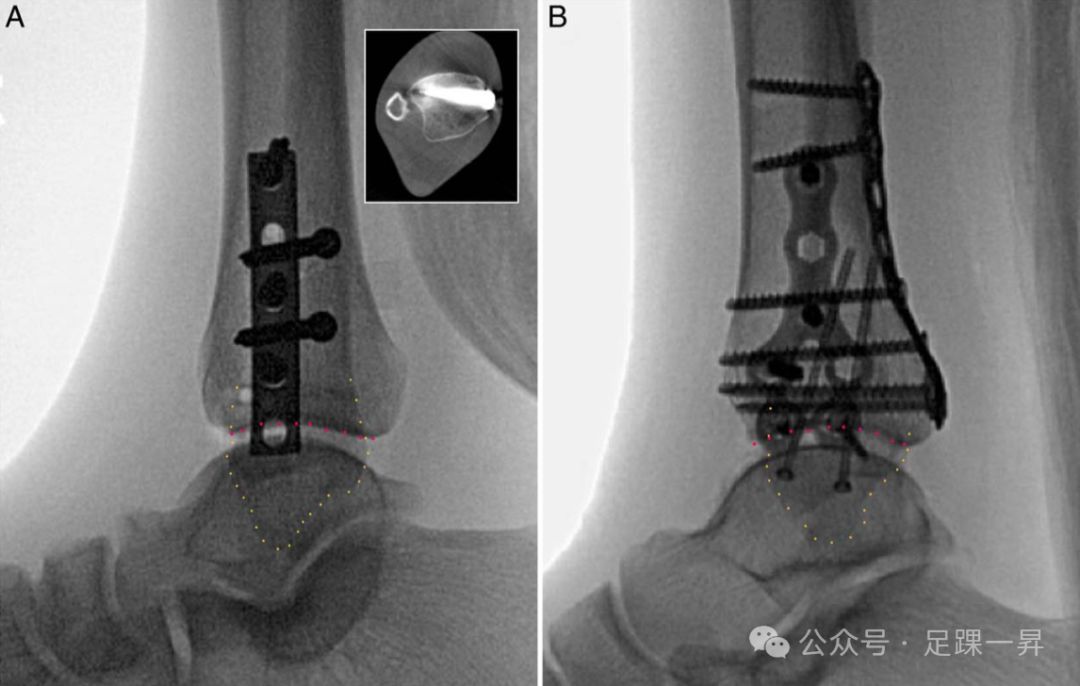

图3. 术中侧位X线片可通过评估腓骨与胫骨的相对位置帮助识别下胫腓联合复位不良。A. 复位不良患者的术中侧位透视图像(如白色方框内的术后轴向CT图像所示)显示,与对侧未受伤侧的前端相比,腓骨相对前移(黄色圆点标记)。通过与未受伤对侧进行双侧对比,可能有助于评估复位的充分性。CT所示为胫骨远端关节面(红色圆点标记)。这与解剖复位患者的图像(如图B所示)不同。